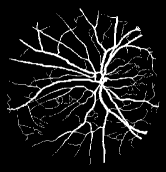

As pointed out in recent works [15, 17], a good semantic segmentation network should learn multi-level features. Further, it should have multiple stages with different receptive fields to learn more inherent features from different scales. FCN, taken as an example, uses skip connections to fuse multiple stages outputs, as well as the HED network, in which a series of side-output layers are added after each stage in VGGNet. The HED network was first proposed for edge detection, and further used for image-level vessel segmentation in recent studies [6, 16], with significant performance. However, our experimental results show that such network architecture is not appropriate for vessel segmentation directly. Figure 1 provides such an illustration. Reasons for this phenomenon are straightforward. On one hand, the side-output of the first layer often contains too many noises. On the other hand, the features produced by the last side-output layer are too coarse due to information loss of pooling operation. Obviously, the inaccurate vessel map of side-output1 and side-output4 should have negative impacts on the final segmentation result.

With the deepening of DSN network, the receptive field of each side-output layer gets larger, which makes the corresponding vessel map much blurrier as observed from the first row in Figure 1, especially for side-output4. These observations inspired us to pass low level fine semantic information to high levels to alleviate the blurring situation.

Bottom-top short connections aim to refine high-level segmentation results. However, we can observe from the first two rows in Figure 1 that the vessel map generated by the first side-output layer contains too many noises while the map generated by the last side-output could capture the main vessel structure. Therefore, we propose delivering high-level structural information to the first side-output layer to reduce its noises. We implemented this kind of information delivery by a top-bottom short connection from conv4 to feat_conv1, which can been seen in Figure 4. We first convolved the last convolution of conv4 using 1 convolution kernels with size 33. Then the obtained feature map are up-sampled 8 to get feat_4_1. The information (feat_4_1) passed from conv4 are concatenated with feat_conv1 to form feat_conv1_fuse (see Figure 5). At last, one hand hand, we perform a 11 convolution operation on feat_conv1_fuse to get the information (feat_1_2) delivered to feat_conv2. On the other hand, we performed convolution operation with a kernel size of 11 and sigmoid transformation for feat_conv1_fuse sequentially to obtain the segmentation result (side 1). At last, side 1 is compared with the ground truth to get the loss of the first side-output layer.

In addition, we can observe from Figure 1 that the side-output1 and side-output4 of the BTS-DSN were more accurate compared with those of the DSN.

The segmentation results of image-level input BTS-DSN on three datasets are shown in Figure 6. We can observe from Figure 6 that the binary vessel segmentation results of BTS-DSN can recognize very coarse vessels. However, for thin vessels, the segmentation results are intermittent and many thin vessels cannot be identified.